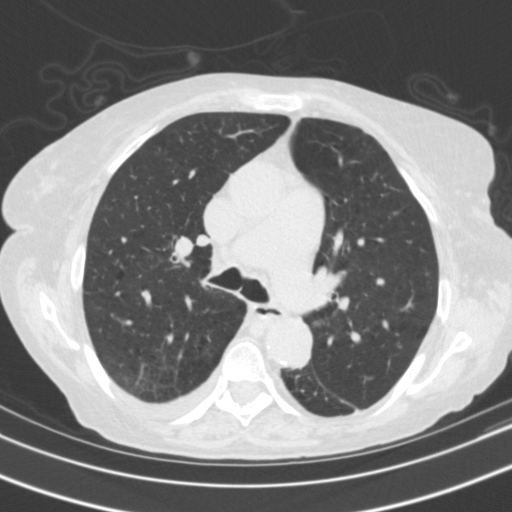

Generated VENOUS CT scan (A→B translation)

Full window (WL 1023.5, WW 4095 β†’ Low βˆ’1024, High +3071)

Lung window (WL -600, WW 1500 β†’ Low βˆ’1350, High +150)

Mediastinum window (WL 40, WW 400 β†’ Low βˆ’160, High +240)